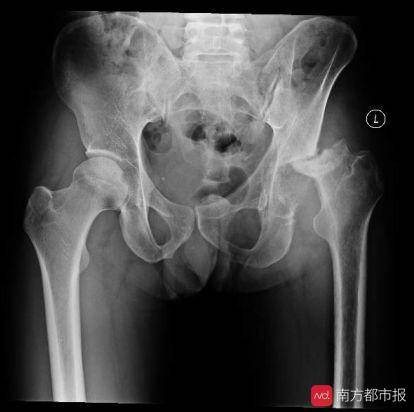

股骨正位-x线图

日饮白酒超半斤 五旬大汉股骨头崩塌